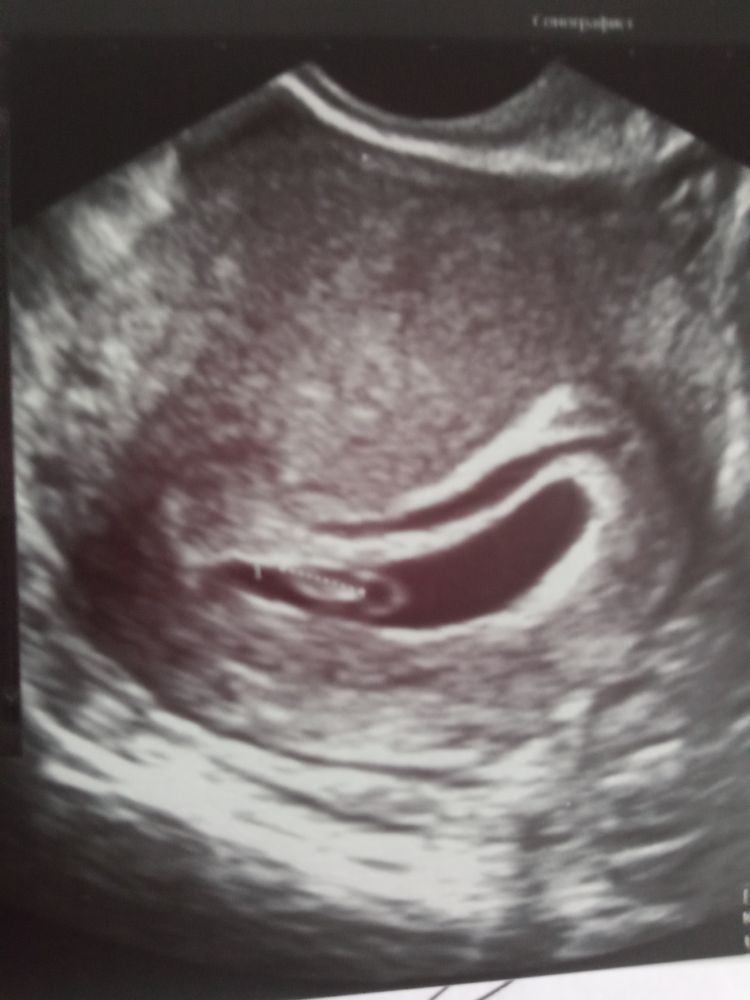

Мое

Мое плодное деформированное яйцо,при самостоятельной беременности,на тот момент ещё и с огромной отслойкой.фотка рядом результат который уже лежит рядом.не волнуйтесь.слушайте врачей.многие любят жути нагнать